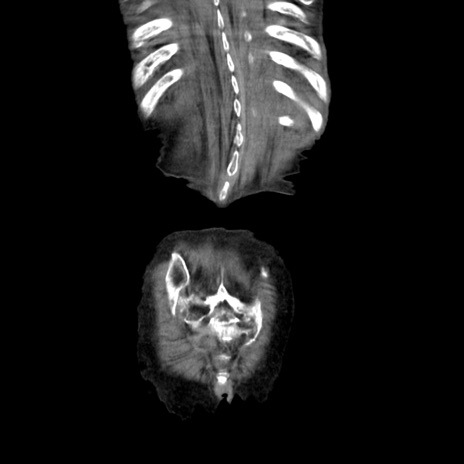

症例27(冠状断像)

症例

【症例】80歳代女性

【主訴】嘔吐、腹痛

【現病歴】数時間前より嘔吐あり。心窩部痛出現し、徐々に右下腹痛あり。その後も数回嘔吐あり救急搬送となる。

【既往歴】左大腿骨頚部骨折手術

【身体所見】腹部は膨隆しているが軟らかく圧痛なし。腸雑音はやや亢進。

【データ】WBC 12000、CRP 19.05